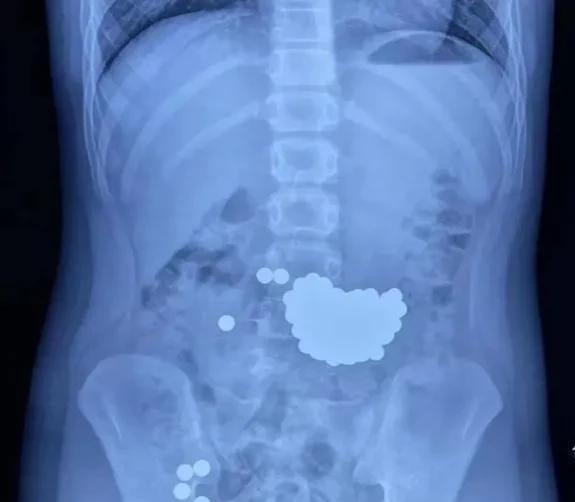

10岁男孩吃掉100粒小钢珠,重约203.3克,医生60分钟取出92颗

当地某儿童医院的医生,经过B超检查,看到男孩的胃里,有好多小钢珠,有的钢珠,已经进入了肠道。

取钢珠,要通过胃镜,才能取出来。钢珠很多,医生取了20多次,每次取四五颗。

一个多小时后,医生取出了92颗钢珠,还有11颗留在肠道里。

取出的钢珠,经称重,有203.3克。